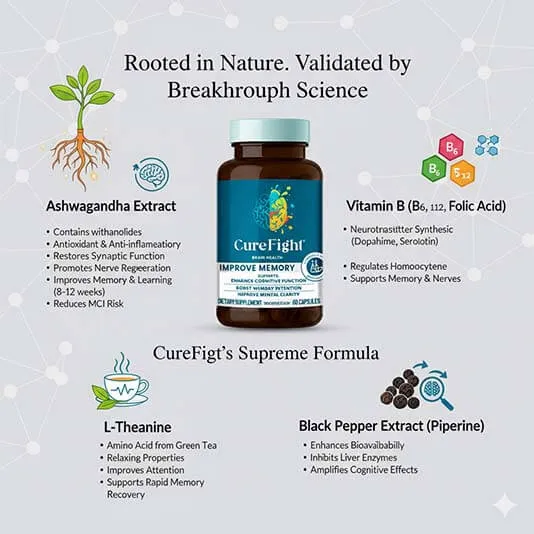

CureFight's Supreme Formula is sourced directly from nature's most potent cognitive healers and meticulously refined in a laboratory setting. Unlike weak, single-ingredient pills that only offer temporary energy, our formula targets the core issue of cognitive decline by combining essential nutrients with powerful, clinically effective extracts.

● Ashwagandha Extract: Contains active compounds like withanolides, offering antioxidant and anti-inflammatory benefits, it restores synaptic function, promotes nerve regeneration, and slows neuronal degeneration; studies show that long-term use (8-12 weeks) may significantly improve memory, learning ability, stress resilience, and reduce the risk of mild cognitive impairment progressing to dementia.

● Vitamin B: Includes B6, B12, and folic acid, participating in the synthesis of neurotransmitters (such as dopamine and serotonin) and the regulation of homocysteine metabolism, providing direct support for memory and nervous system health.

● L-Theanine: An amino acid found in green tea with relaxing properties, it improves attention and supports rapid memory recovery by regulating neural excitability.

● Black Pepper Extract (containing piperine): Primarily enhances the bioavailability of other ingredients (such as ashwagandha or L-theanine) by inhibiting liver enzymes, amplifying the cognitive support effects of the combined formula.